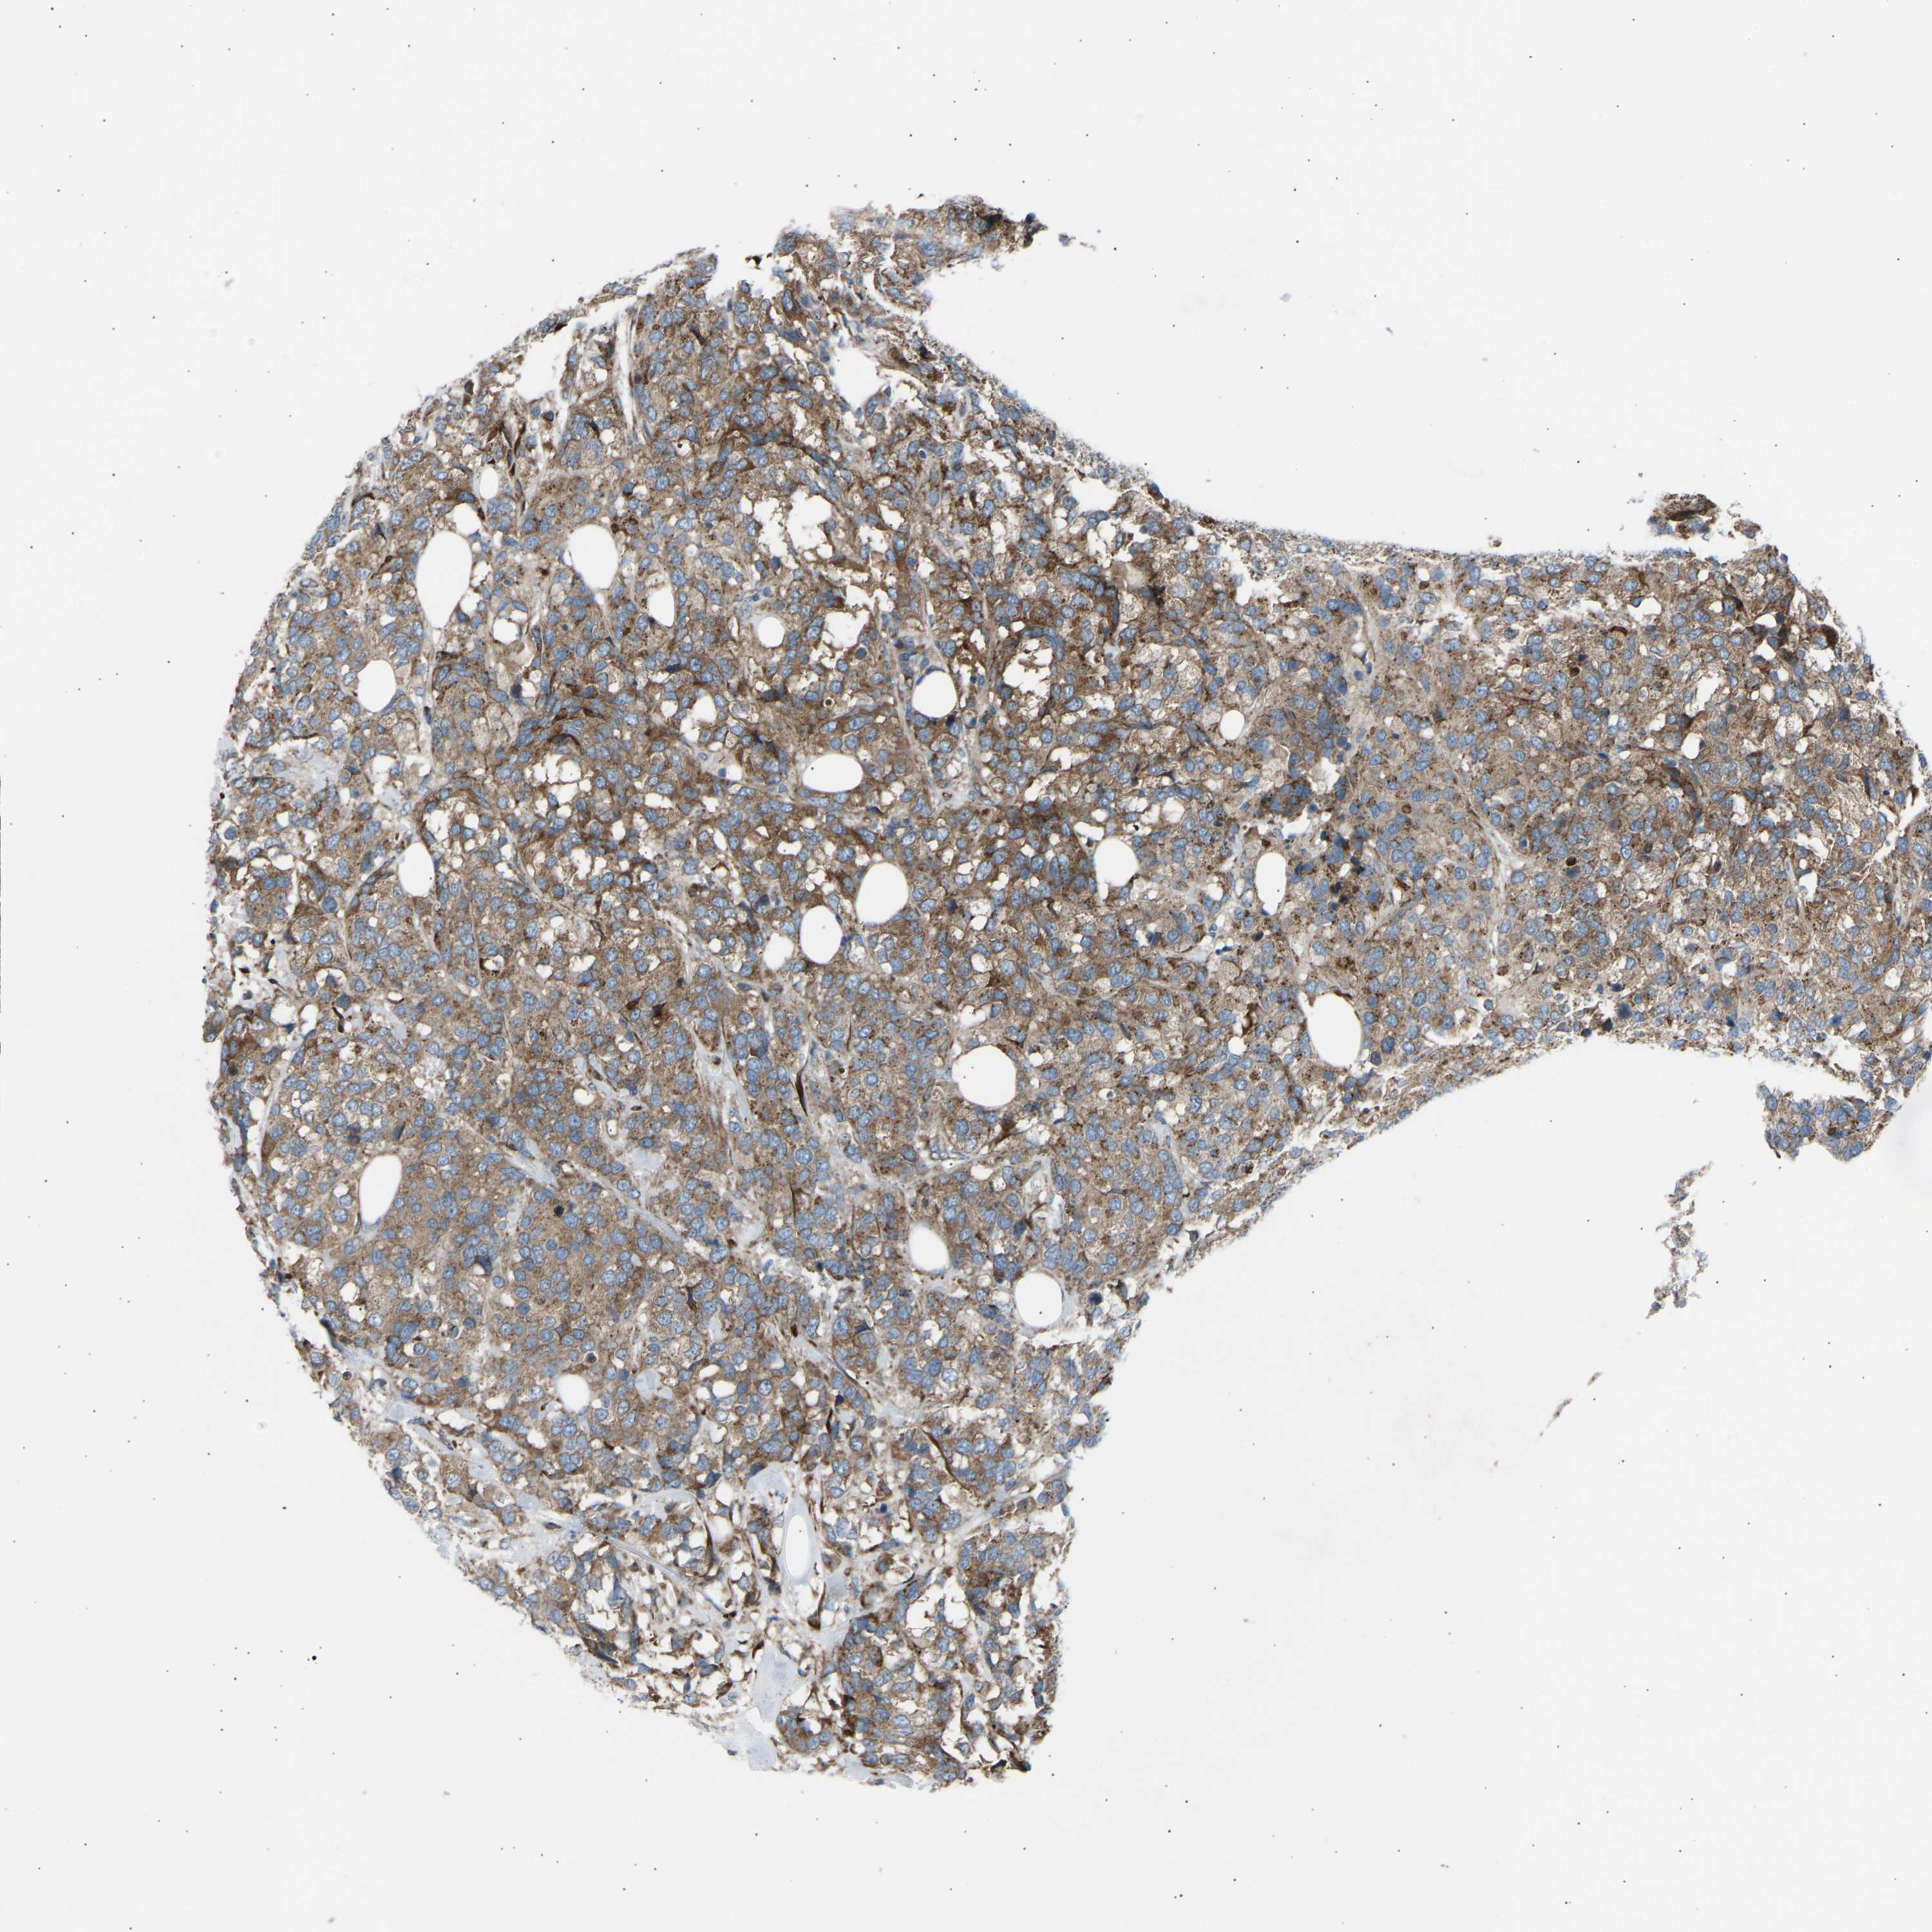

CANCER BREAST CANCER Show tissue menu

BRCA TCGA BRCA VALIDATION PROTEIN EXPRESSION

Breast cancer

Human cancer

Breast invasive carcinoma